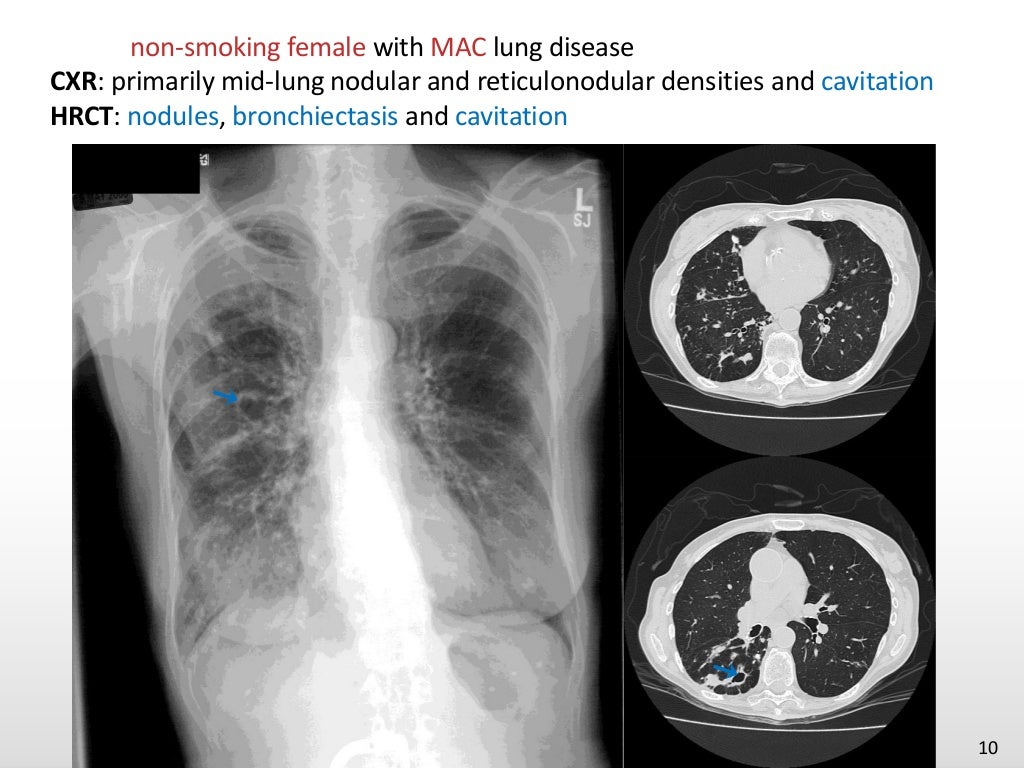

Chest imaging of ntm pulmonary disease2 What Causes Ntm Lung Disease nontuberculous mycobacteria (ntm) infections are an underrecognized source of lung disease associated. ntm also can cause substantial pulmonary pathology, both in immunocompetent and. what causes it? nontuberculous mycobacteria (ntm) are a group of ubiquitous environmental bacteria that can be found. Ntm comprise more than 190 different species (types) of bacteria that are found naturally in the. What Causes Ntm Lung Disease.